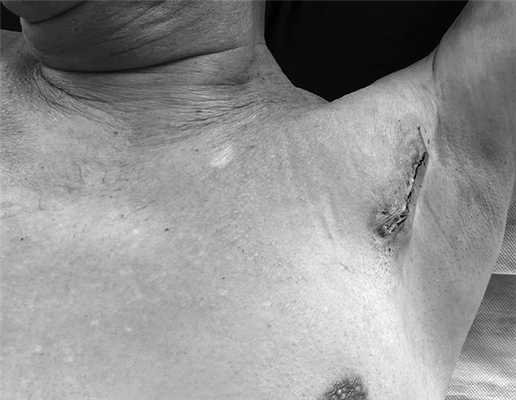

Таким образом, осуществлена трансаксиллярная эндовидеохирургическая безгазовая дивертикулэктомия. Дренирование и послойное ушивание раны. Продолжительность операции составила 137 мин: доступ — 35 мин, мобилизация дивертикула — 38 мин, интраоперационная эндоскопическая навигация и отсечение дивертикула — 25 мин, ушивание стенки пищевода и раны — 39 мин. Антибактериальный препарат ввели однократно в день операции. На 2-е сутки выполнили рентгенографию с водорастворимым контрастным препаратом. Признаков несостоятельности швов или сужения глоточно-пищеводного отдела нет (рис. 5). Дренаж удален (рис. 6). Пациенту разрешили пить, а с 3-х суток — принимать жидкую пищу. Клинических признаков повреждения возвратного гортанного нерва не отмечено. В удовлетворительном состоянии пациент выписан на 7-е сутки после операции. Осмотрен через 1 мес после вмешательства. Чувствует себя хорошо, жалоб не предъявлял, питался в полном объеме.

Рис. 6. Зона оперативного вмешательства и формирующийся послеоперационный рубец (послеоперационная фотография).